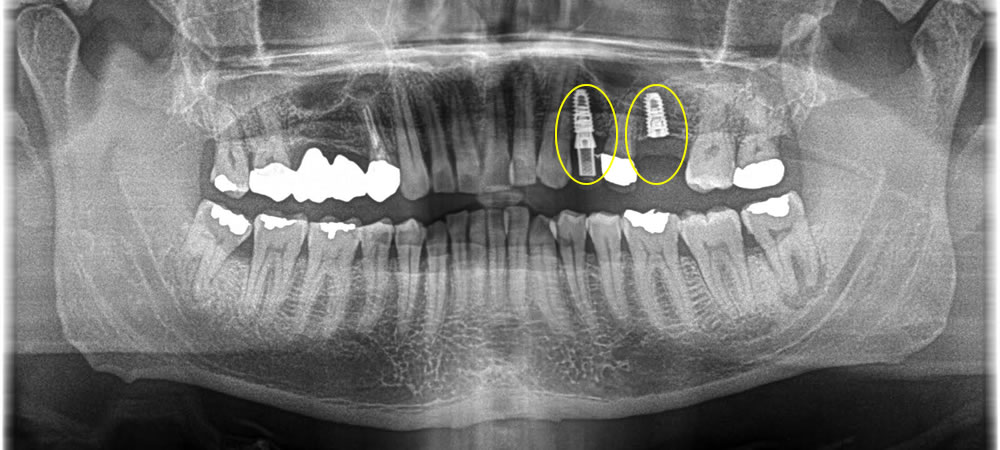

手前の歯は審美的に気になるという事でした。当該部分は骨がしっかりとあり、即時荷重が可能な状態なためインプラント埋入と同時に仮の歯を装着しました。また、手前の歯は6ミリ程度の切開で行ったため、縫合もなく痛み腫れもほぼ無く施術できました。

その後、3ヵ月待ちしっかりと骨と結合しているのを確認後、上部のジルコニアの歯を作成しました。最終的に残りの真ん中の歯も綺麗にしたいとの事で、セラミッククラウンにて治療を行いました。